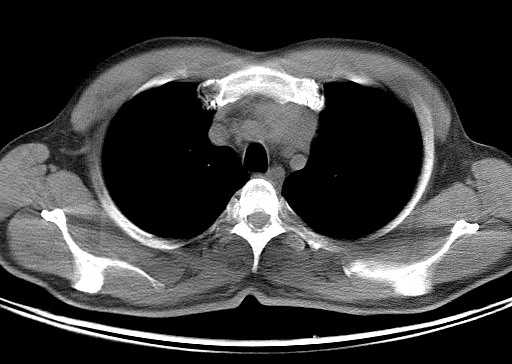

男   40   反复腹痛入院行彩超检查示胸骨右缘4、5肋间不均质回声团

淋巴瘤:前纵隔可见多组肿大的淋巴结,部分融合,有液化坏死

纵隔恶性肿瘤,考虑生殖细胞肿瘤可能性大。